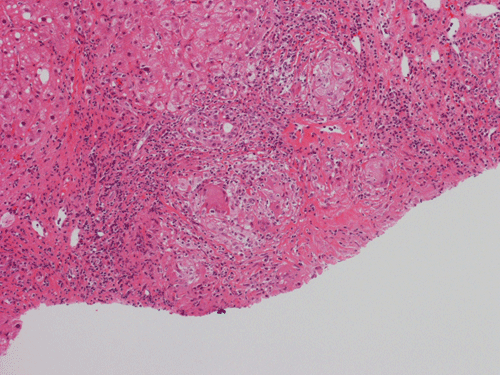

Pathology of the Case: At low magnification, a few small nodules (arrow in Panel A) can be seen with the hematoxylin and eosin stained section. On medium magnification, these nodules correspond to sharply defined granuloma without necrosis. These granuloma are not associated with a high density of lymphocytes in the surrounding liver parenchyma (Panel B and C). Multinucleated giant cells (arrow in Panel C, magnified in Panel D). On reticulin stain, there are reticulin fibers that extends into the granuloma (Panel E). Trichrome stain demonstrated bridging fibrosis (Panel F). The granuloma are well defined and some of them are surrounded by fibrous tissue (Panel G). Immunohistochemistry demonstrated preservation of bile ductules as well as proliferation of ductules (Panle H). No residual ductules are noted in the granuloma as revealed by immunohistochemistry for CK7 (Panel I). Neither acid fast bacilli or fungal organisms are identified by acid fast stain and Gomori's methenamine silver (GMS) stain.

Histopathologic features of sarcoidosis include scattered granulomas in the liver, which may tend to be portal or periportal. Multinucleated giant cells, epithelioid cells, and a variable but usually minimal inflammatory cellular response is present. The granulomas, like in sarcoidosis occuring in other organ systems, tend to be well-demarcated or "clear cut", several granulomas are often comparable in size, and necrosis is not typically present. Asteroid bodies, intracellular vacuolated structures resembling a sea anemone, may be found within the giant cells. Large basophilic, round to roughly oval, and concentrically laminated, Schaumann bodies may be evident in the sarcoid granuloma. None of these inclusions are pathognomonic feature of sarcoidosis, however, do suggest this diagnosis. Ductopenia, cholestasis and features of chronic cholestasis resembling PBC have been described in the cases of sarcoidosis. Severe fibrosis and cirrhosis in conjunction with portal hypertension may be present in sarcoidosis. End stage liver disease in sarcoidosis has been successfully treated by orthotopic liver transplant and recurrent disease has been reported in one such case. Reticulin fibers has a tendency to extend into the granulomas as illustrated in this case.